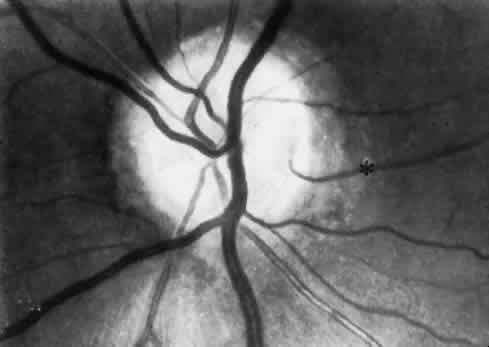

In as many as 20% of normal eyes, a cilioretinal artery may exist as well.11 These are vessels that directly connect the posterior ciliary circulation to the retinal circulation. Clinically, they can usually be identified by their ophthalmoscopic appearance. Cilioretinal vessels emerge from the edge of the optic disc, with no apparent connection to the central retinal vessels (Fig. 2). Fluorescein angiography shows them to fill with the choroidal circulation. They are usually temporally located on the optic disc but rarely can be nasal. Multiple vessels may be present. Cilioretinal arteries are the easiest to identify. The existence of cilioretinal venous channels in normal eyes is a subject of debate.12 Acquired cilioretinal veins, referred to as optociliary anastomoses or incorrectly as optociliary shunts, can develop in pathologic processes such as obstruction of the CRV or in optic nerve tumors (Fig. 3).

Fig. 3. An opticociliary vein developing in an elderly patient after a central retinal vein occlusion. The vein appears as a tortuous vessel, inferotemporally (arrow). (Henkind P, Benjamin JV: Trans Ophthalmol Soc UK 96:418, 1976)